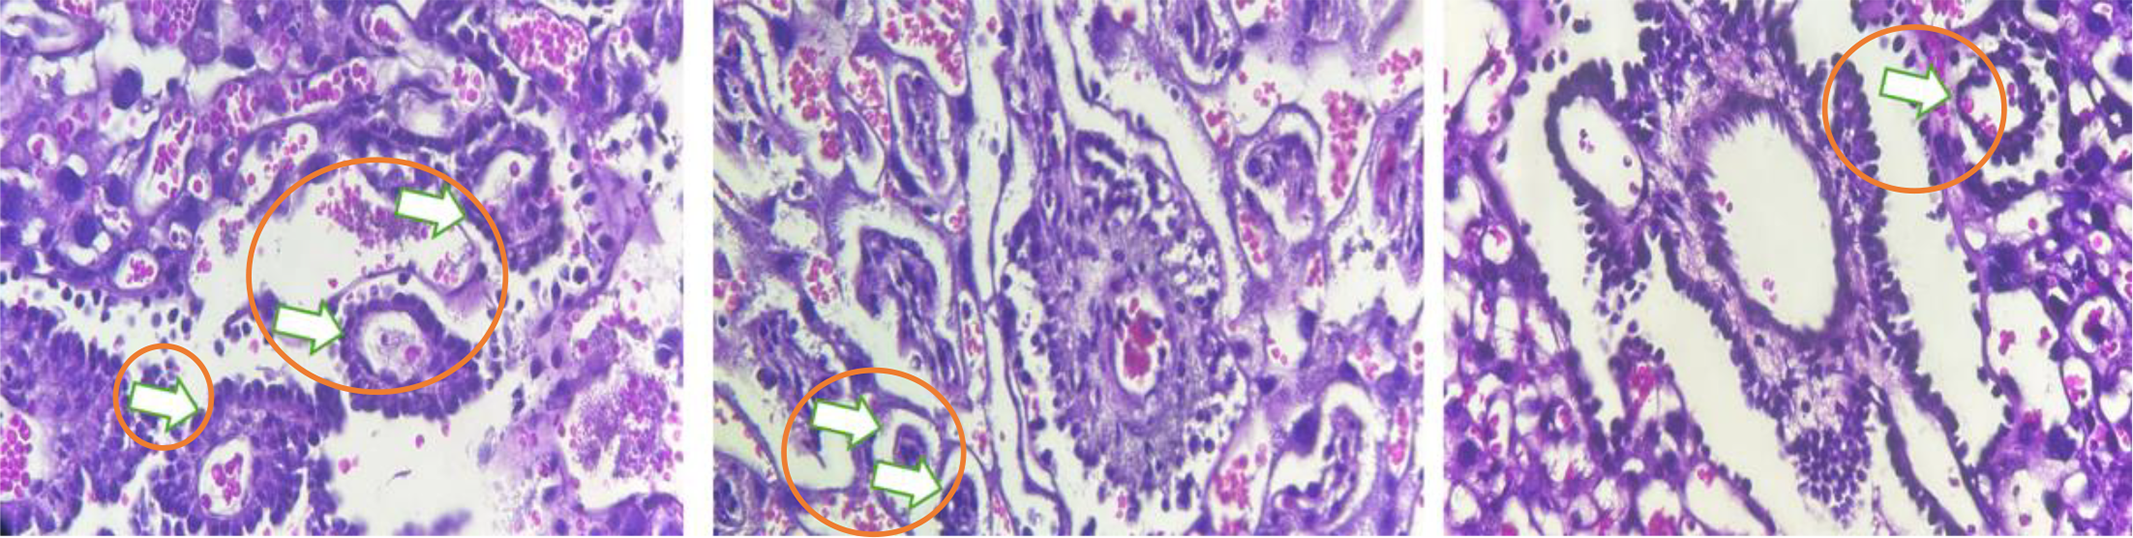

This histological image of placental terminal villi, the smallest villous structures, illustrates their role in nutrient and gas exchange between the mother and fetus. The villi appear as small, finger-like projections covered by syncytiotrophoblasts, which facilitate the diffusion of oxygen, carbon dioxide, glucose, and amino acids. (Shown by the arrow on the Fig. 2) The core contains loose connective tissue and mesenchymal cells, while blood capillaries lie close to the outer syncytiotrophoblast layer to maximize nutrient exchange. The Hematoxylin and Eosin (H&E) staining highlights cell nuclei in purple and the surrounding tissue in pink. The dense red blood cells within the capillaries are clearly visible as dark red areas.

Fig. 2. Histology of the number of terminal villi.

A large number of terminal villi indicates a metabolically active placenta, enhancing the surface area for maternal-fetal exchange. Pathological conditions such as placental insufficiency or preeclampsia may reduce villous numbers or cause fibrosis. This image shows healthy villous structures, confirming normal placental function.